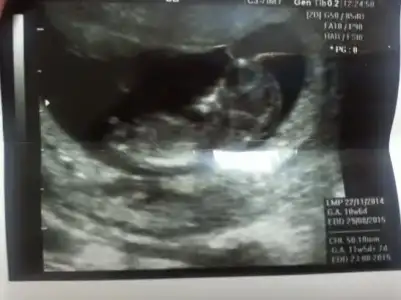

merhaba benim bebişiminde resmi bu 11-3 haftalıkken yorum yapabilirmisiniz

• CAM01704[1].webp

CAM01704[1].webp

29,8 KB · Görüntüleme: 117